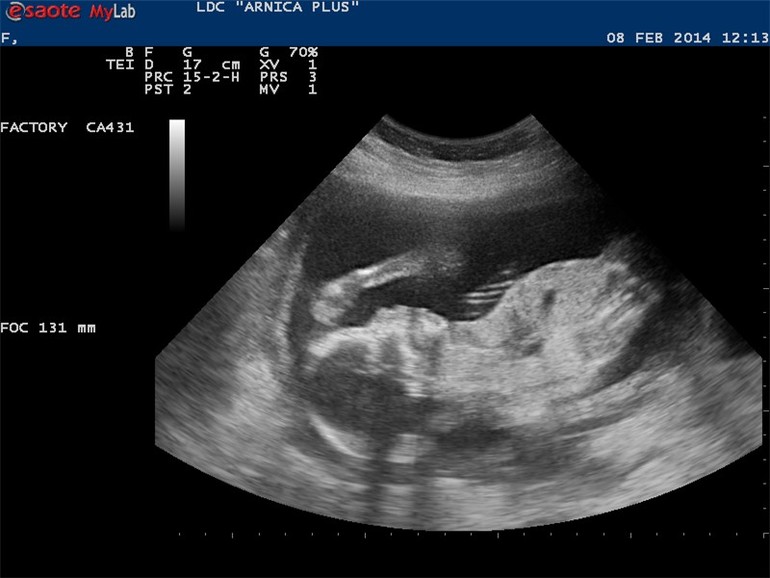

Второе УЗИ )))

Беременность 2013-2014 г.Мега-позитив! Все мои страхи , что малышонку в пузике не очень хорошо РАЗВЕЯЛИСЬ ( причина - инфекции в организме, хр. заболевание почек). Тонуса нет, низкое прикрепление ПОДНЯЛОСЬ)), развивается в срок - в общем все отлично!

Узистка смеялась, "мыслитель" великий назвала)))

У нас тоже УЗИстка поймала фас , но мне не очень нравится, т.к. выглядит как скилетик из фильмов ужасов)))) - большие глазницы, косточка носика ,черип , а в профиль человечик как человечик))) щечки, губки даже видно

Всего у нас 6 фото, это мое любимое))